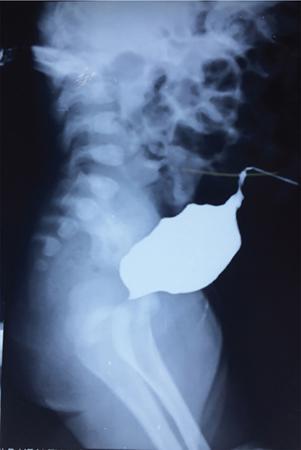

• Male patient – steep oblique position is optimum (Fig. 10.6.9).

• Female patient – anteroposterior view is preferred which will show a classical spinning top appearance (Fig. 10.6.10).

• This image will depict abnormalities of the posterior urethra like posterior urethral valve, outlet obstruction as well as point towards a possible VUR (Fig. 10.6.11). One image can be obtained with the catheter in situ and another with the catheter removed. Voiding with catheter in situ allows refilling if needed and drain bladder in patients who are unable to void completely. A neurologic abnormality, bladder spasm or active bladder infection can be indicated by low voiding volumes. However, reproducibility of these findings should be documented for this observation to be reliable. An unexpectedly large bladder capacity may be seen in sensitive voiders, dysfunctional voiding or noncompliant recently trained children. May be due to noncompliance in recently toilet-trained children.

Fig. 10.6.9 Normal appearance of a male urethra on an MCU. Yellow arrow points towards the prostatic urethra. The bulbar portion is marked by the arrowhead. Between the two lies the membranous urethra and distal to the bulbar urethra lies the penile urethra.